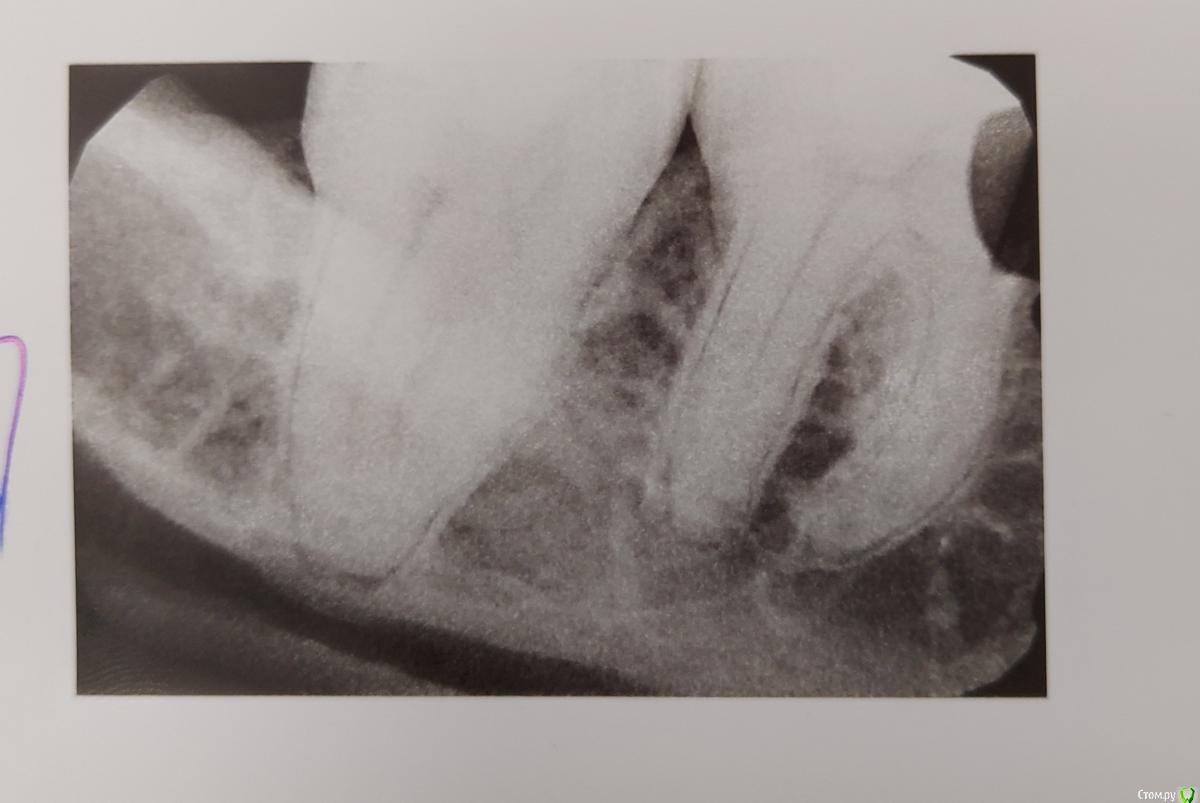

6,7 зубы на нижней челюсти

По ночам возникает дискомофорт в районе 6 и 7 зубов нижней челюсти.

Сделал снимок, но к врачам не обращался, в командировке.

6й зуб был запломбирован 12 лет назад, и никогда не беспокоил.

Подскажите, есть ли повод для беспокойства.